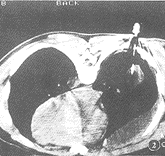

图8,9 女,46岁,肝右叶6 cm×6 cm×6.4 cm肝脓肿,介入治疗抽脓液40 ml,冲洗后注入庆大霉素32 万U,细菌培养药敏试验后用呋喃妥因治疗,14 dB超复查脓肿消失